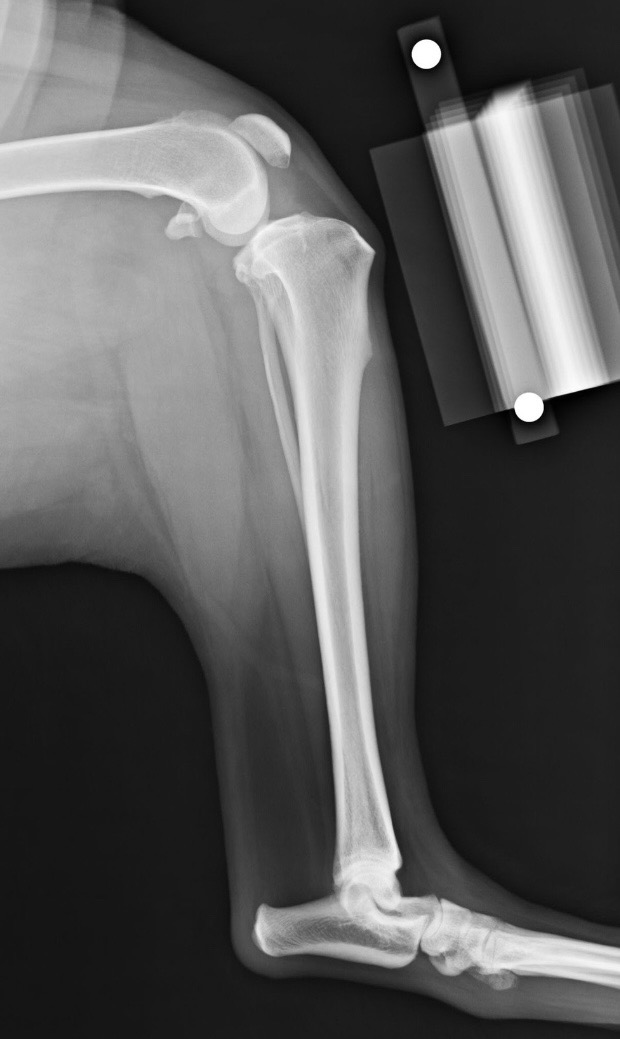

哈士奇嚕嚕 十一月初外出散步時發現左後腳偶爾不太負重,主人非常細心的觀察到嚕嚕在慢走時左後腳會踩,但快走時就會成三腳走,在他院開消炎止痛藥後沒有改善就到本院進一步檢查。

理學檢查下抽屜試驗及脛骨施壓試驗發現異常懷疑十字韌帶有受損,和主人討論後續治療並且鎮靜拍x光評估脛骨平台水平矯形術(Tibial Plateau Leveling Osteotomy ; 簡稱TPLO)